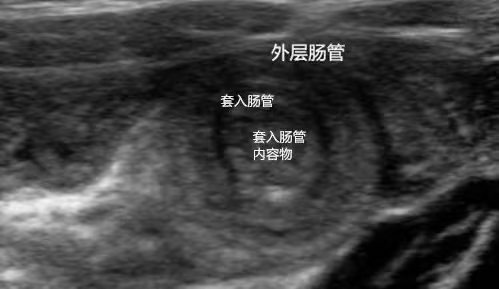

肠叠套肠套叠是6个月至2岁儿童高发的肠道疾病,指一段肠管套入相连肠腔导致内容物通过障碍,需警惕宝宝莫名哭闹等症状一主要症状与体征阵发性哭闹宝宝在精神充沛时突然剧烈哭闹吼叫,脸色苍白冒冷汗,腹部翻挺哭闹难以安抚,发作间歇期可能短暂恢复活力,但多次发作后间隔缩短,间歇期易。

肠套叠是一段肠插入相邻的肠段,导致肠梗阻和肠道不畅的现象理论上,肠的任何部分都可以发生,但大多数发生在小肠和大肠的连接处这是宝宝最常见的急腹症如果宝宝肠套叠持续1 2天,肠套叠肠的血液循环受阻,肠套叠越紧,可能会危及宝宝的生命对于严重肠套叠的宝宝,应采用剖腹手术和肠套叠管复位。